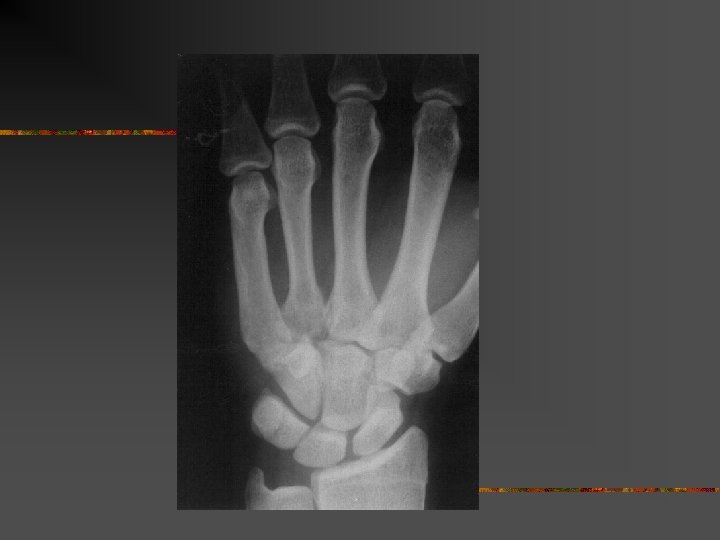

Radiographie n n n Face et profil de la MP Arrachement articulaire Subluxation palmaire

Radiographie : subluxation palmaire

Le problème : n n n Évaluer la grâvité de l’entorse : Pas grave = Tt orthopédique Grave = Tt chirurgical n. Clichés dynamiques